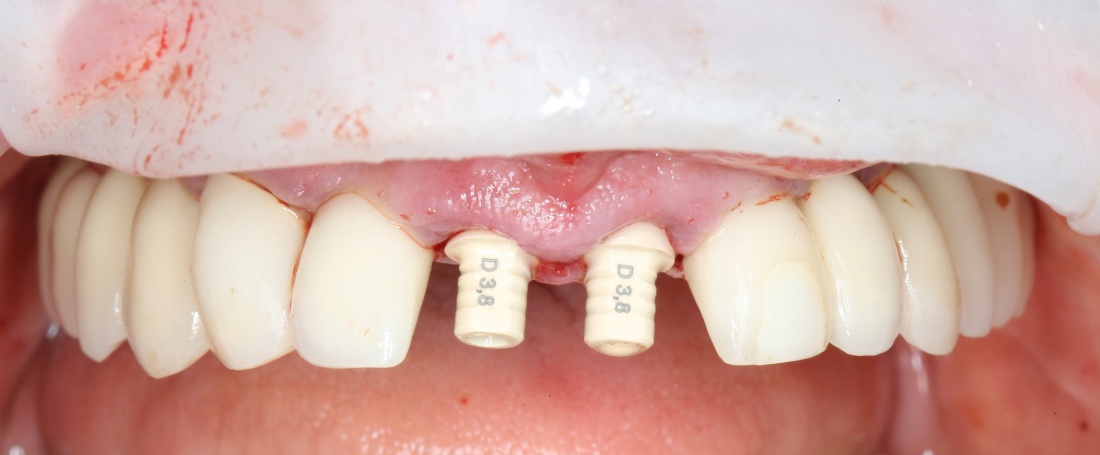

Вот пример. В нашей клинике мы используем три имплантационные системы компании Dentsply Sirona Implants: XiVE, Ankylos и Astratech. Они существенно различаются по макродизайну. Более того, в отличие от субгингивальных XiVE и Astratech, Ankylos — это субкрестальная система, предполагающая погружение платформы ниже уровня альвеолярного гребня.

Это значит, что использовать имплантаты Ankylos при расстоянии до дна синуса менее 2 мм будет проблематично (но возможно, см. клинический пример). Там, конечно, есть специальные заглушки и всё такое… но, к чему этот геморрой?

Импланты Astratech Osseospeed TX, имеющие расширяющуюся пришеечную часть (4,5 и 5.0 мм) также использовать в таких условиях (1-2 мм до дна) сложновато. И дело тут уже не в имплантате, а в хирургическом протоколе — чуть перекрутил кортикальной фрезой, и имплант проваливается в пазуху

Зато в таких условиях отлично стабилизируется XiVE и, внезапно, Nobel Replace, еще внезапнее — Dentium (последние два мы не используем в практике):

Поэтому, если на практике встаёт вопрос о синуслифтинге и имплантации при незначительных (менее 2 мм) расстояниях до дна верхнечелюстного синуса, возможность стабилизации является одним из факторов выбора имплантационной системы для конкретного клинического случая. Учитывайте это, планируя лечение пациента.

решение о проведении имплантации одновременно с синуслифтингом принимается, исходя из возможности стабилизации имплантата в существующем объеме костной ткани. А это, в свою очередь, зависит от макродизайна импланта и хирургического протокола при его установке.